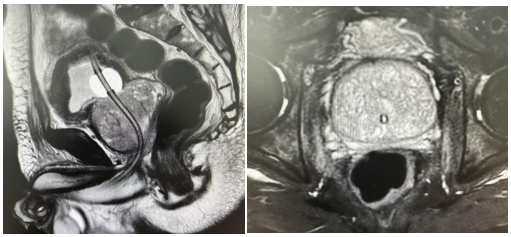

入院后检查发现,常师傅的前列腺体积达到了惊人的7×6.7×5.4cm,重量约132 克,是正常前列腺的7倍之巨,同时还伴有糖尿病和心脑血管疾病。面对如此棘手的情况,医院泌尿外科迅速组织多学科会诊。专家们精心制定方案,先用胰岛素泵精准控制血糖,麻醉科选择腰麻半身麻醉确保手术安全,手术方式则采用全新引进的蓝激光经尿道汽化术。在泌尿外科冯中文教授团队的精湛操作下,手术过程十分顺利,仅耗时40分钟,术中几乎不见出血。术后常师傅恢复良好,尿管内尿液清澈,72小时后拔除尿管,排尿通畅且无尿失禁现象,多年的顽疾一朝得解,告别了常年服药的日子。此次手术的关键 —— 蓝激光手术设备,是我国自主研发的全球首创成果。与传统激光相比,蓝激光对血红蛋白具有高度亲和力,能高效汽化组织,同时具备出色的凝血能力和低组织穿透性,对周边组织热损伤极小。医院引进的200W蓝激光手术系统更是目前世界领先,其高功率、高汽化速度为前列腺增生治疗开辟了全新模式。无论是较小的增生腺体,十几分钟即可完成手术,还是像常师傅这样的巨大腺体,手术也能在半小时左右高效完成。蓝激光汽化术以其高效、快速的优势,拓宽了手术适应症范围,极大降低了手术风险,为高龄高危前列腺增生患者带来了福音。